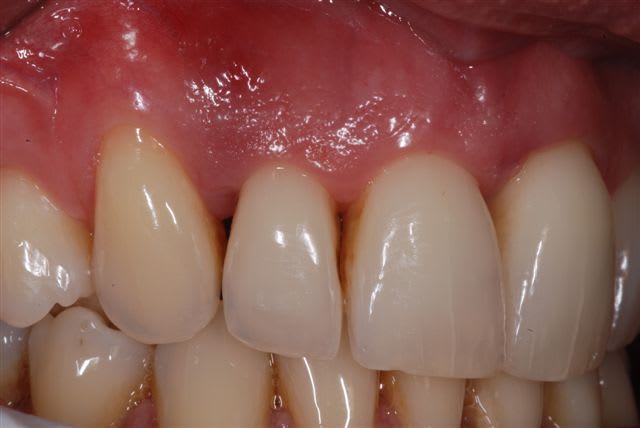

Dans la meme veine , ce patient de 50 ans est venu avec un abces paro en vestibulaire de 17 .Antécédent de traitement parodontal , hygiene à améliorer , passe les brossettes ,fumeur .La 17 est vivante , peu de gencive attachée , poche relativement localisée 1mm distal , 20 mm en regard de la racine mesiale pas d'atteinte de la furcation , 10 mm entre 16.17 avec atteinte de la furcation .

Pensez vous qu'un curetage soigneux ,comblement avec membrane soit envisageable ? ou dévitalisation ,extraction de la racine MV ? ou extraction totale ?

En ce qui concerne la 17, le niveau de perte osseuse semble être à la vue de la radio beaucoup plus important que celui que tu sembles décrire au sondage. Les racines sont regroupées, le tronc furcatoire profond ce qui rend l'appréciation des atteintes de furcations difficile.

En ce qui concerne la 16 le niveau de perte osseux est tout aussi important avec une atteinte de furcation de grad 2+ voir 3 en vestibulaire et proximal. La perte osseuse interradiculaire semble plus que manifeste radiologiquement, également en vestibulaire de la racine palatine.

En raison de la perte osseuse importante, du profil des défauts osseux, des atteintes de furcations, tu ne peux espérer obtenir une régénération parodontale. La littérature scientifiques a largement décrit le traitement des molaires maxillaires avec atteintes de furcation : modalités, résultats, pronostic et alternatives. Va faire un tour sur medline. La parodontologie tout comme le reste de la dentisterie n'est pas une cuisine ou un atelier de mécanique !! Les stratégies thérapeutiques doivent être basées sur des preuves scientifiques.

En ce qui concerne les amputations radiculaires, elles ne permettront pas d'améliorer le pronostic. (cela aurait du être dait dans ce cas bien plus tôt).

Le pronostic de 17 et de 16 n'est pas réservé, il est mauvais et ces dents sont à extraire.

Lors de l'extraction tu peux également en profiter pour traiter le défaut infra-osseux en distal de la 14.